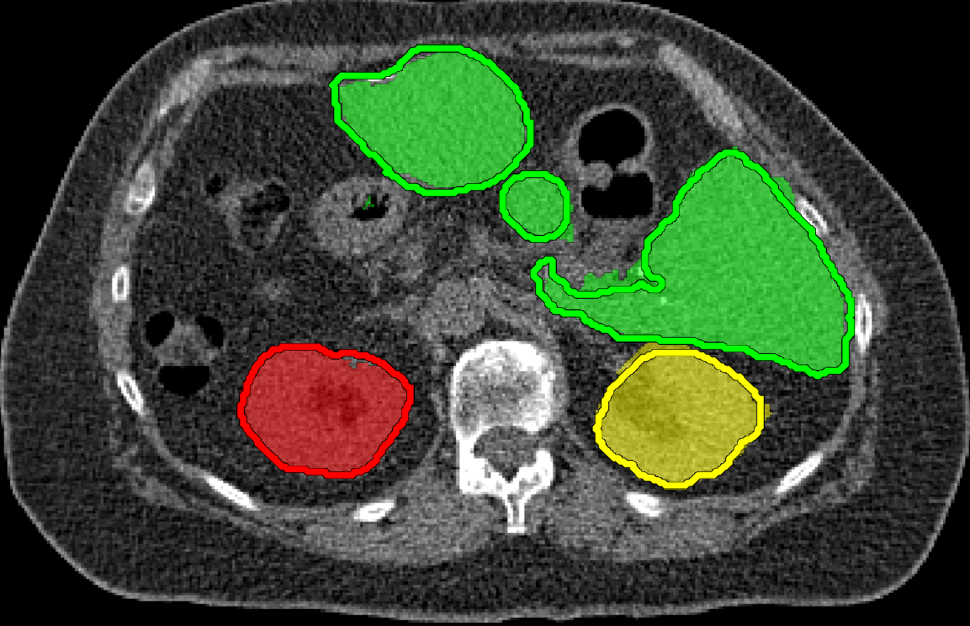

We applied our method on PET-CT scans of three different subjects to segment their liver, left kidney, right kidney and the background. Although we applied our method and Potts model on the 3D volumes we only show the results on a few representative slices from each volume in Fig.11. Also, the results of different methods for each subject were computed using the same smoothness. We can see from the last two rows which compare our method to Potts, using Hedgehogs constraints enabled us to avoid geometrically incorrect segmentations, e.g. one liver inside the other (last-row middle), or parts of left kidney is between the right kidney and liver (last-row right). Furthermore, for test subjects 1 and 2 the kidneys and background were poorly segmented by Potts model, e.g. most of the kidneys were segmented as background for test subject 1. Potts poor performance is due to the large overlap between the kidneys and background color models. This overlap resulted in an in-discriminative data term for Potts to properly separate them. This issue becomes worse in iterative frameworks where color models are re-estimated based on current segmentation. To be specific, if at any iteration Potts model resulted in a bad segmentation then re-estimating the color models will bias them towards the bad segmentation and subsequent iterations worsen the results. Comparing our results for subjects 1 and 2 to Potts model shows that our method is less prone to the aforementioned issue as we forbid undesirable segmentations, i.e. those that do not respect shape constraints.

| Subject 1 | Subject 2 | Subject 3 | |||

| Our method (Hedgehogs Shapes + Potts) | ![]() |

|

Potts |

For quantitative comparison, Table 1 lists for each organ of a subject the Score, Precession and Recall measures of our method and Potts model where For the kidneys, our method clearly out performed Potts model, e.g. note Potts model poor precision/recall for subjects 1 and 2. For the liver, both methods performed comparably.